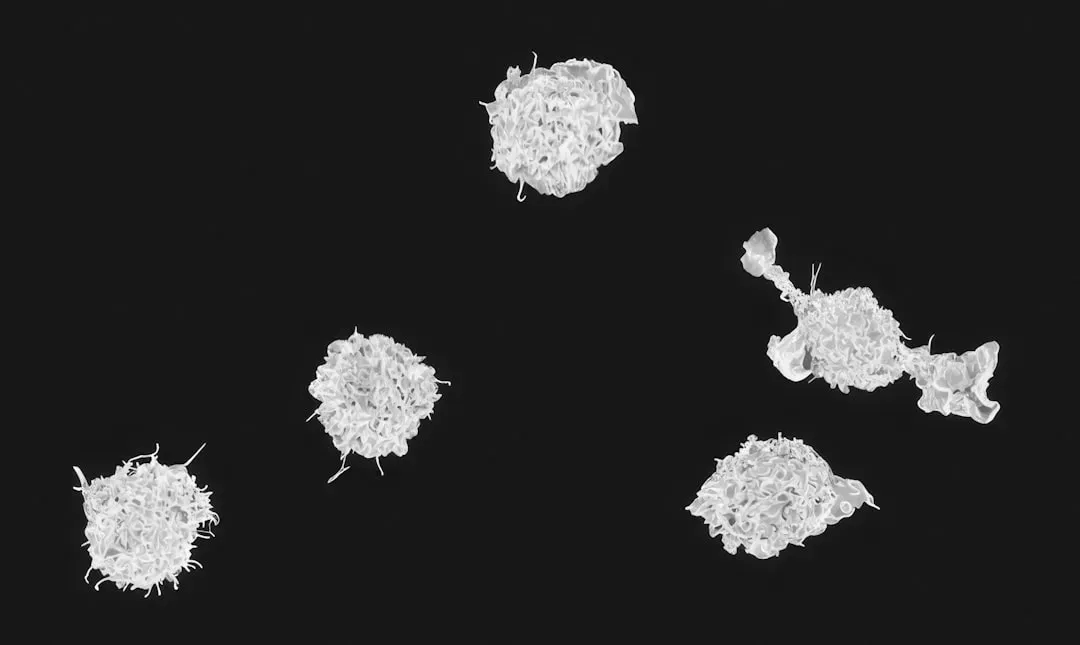

The innate immune system utilizes pattern recognition receptors – like Toll-like receptors – to detect pathogens and initiate rapid response mechanisms. Think of these receptors like molecular bouncers stationed at every door, trained to recognize the “wrong kind” of molecular ID badge. Macrophages and neutrophils of the innate immune system provide this first line of defense against many common microorganisms and are essential for the control of common bacterial infections.

Neutrophils arrive first and can even produce fibers to physically trap microbes, while macrophages phagocytose – meaning they engulf and digest – enormous numbers of invaders. Macrophages hunt for microbes and damaged cells, almost like a biological Pac-Man. It sounds almost too simple to be real, but that is what is happening inside your bloodstream right now.